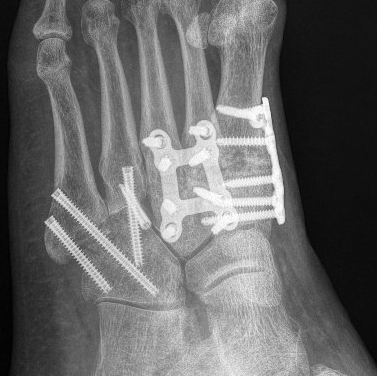

Fusion is permanently stiffening

the bones of a joint together with plates, screws and/or staples. This procedure is also known as arthrodesis.

This surgical procedure involves fusing one or more of the midfoot and hindfoot joints. A common combination is called a hindfoot "triple fusion".